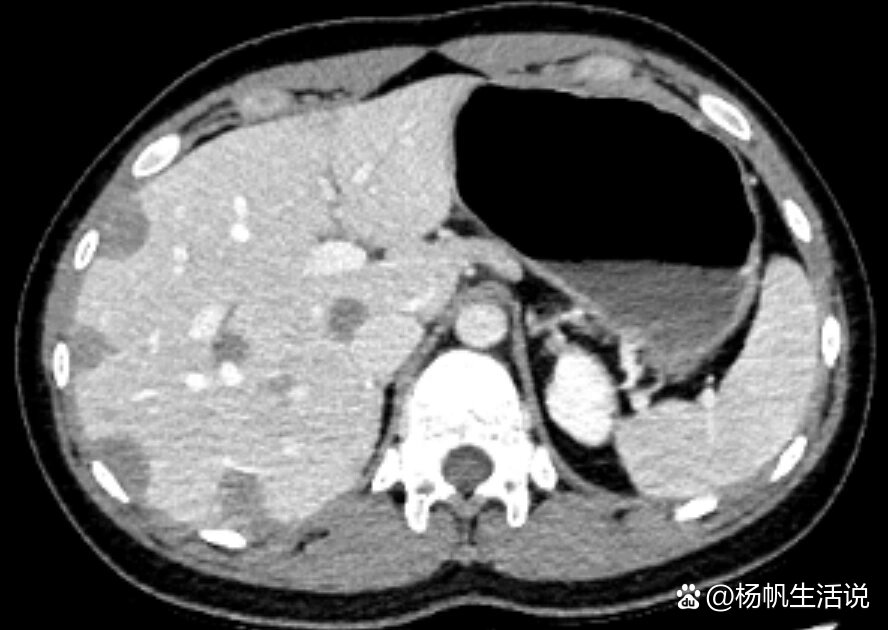

ct),结果显示散在的实性肺结节,数个肝血管瘤和双叶亚厘米级肝脏低

肝血管瘤增强ct表现肝上囊肿和血管瘤有核磁什么区别肝癌的典型超声